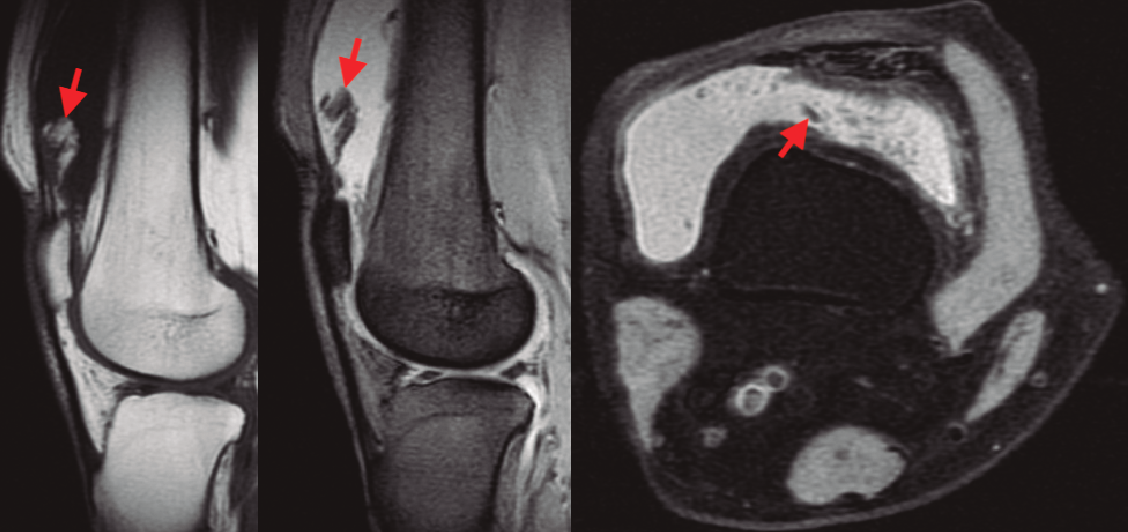

En la resonancia magnética (RM) de los hombros, los citados cambios degenerativos con quistes subcondrales en la cabeza humeral y presencia de cambios inflamatorios en cabeza y troquíter eran evidentes, observándose el LA como una infiltración grasa con vellosidades en la cavidad articular hiperintensas en T1 y T2, con imágenes hipointensas en las ventanas STIR y supresión grasa. También se observó el acúmulo de líquido en la zona de la bursa subacromial (Figura 1), presentando en ocasiones una discreta migración proximal de la cabeza humeral. En ocasiones se evidenció también una alteración de la señal en los tendones del manguito rotador, compatibles en algún caso con roturas. En la RM de los casos de rodilla se evidenció el LA como un crecimiento de partes blandas en la bursa suprapatelar de intensidad compatible con la grasa, asociada a la presencia de derrame articular (Figura 2). Dicha masa era heterogénea, irregular, adherida al plano anterior.

Figura 2. Imágenes en corte sagital y axial de las ventanas T1, T2 y supresión grasa de la RM, evidenciando una masa vellosa en el receso suprapatelar con intensidad de señal grasa, (señaladas mediante flechas), asociada a un derrame articular.